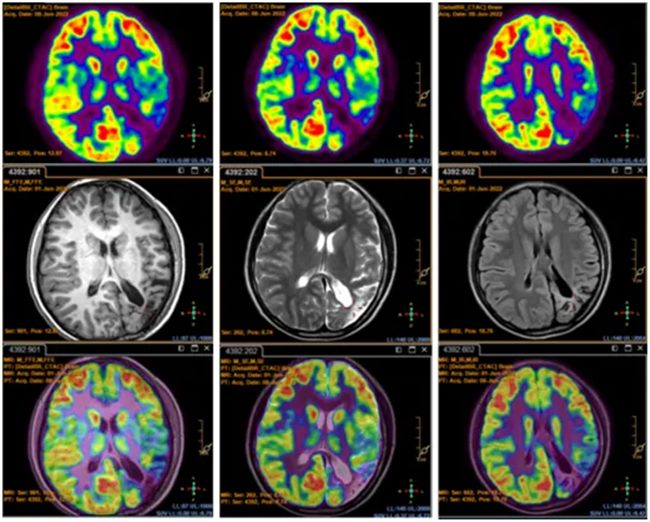

接诊医师为神经外科二病区李信晓博士,通过详细询问病情后,在李培栋主任医师指导下,首先完善颅脑影像学检查和脑电图检查,发现患儿左侧额下回、颞上回、颞中回、颞下回、颞横回、缘上回、角回、顶上小叶、楔前叶、视放射、枕外侧回等广泛受累,大面积软化灶和发育不良等表现。

对于绝大多数人来说,左侧大脑半球是语言和记忆的优势半球,上述任何部位出现问题都可能会影响语言、运动、记忆及视力等。患儿是双利手,年龄小,症状重,药物难治,对于查找引起癫痫的真正病灶难上加难。于是迅速组织癫痫多学科会诊(MDT)和疑难病例讨论,经多位专家对影像分析、脑电图判读、发作临床表现和用药情况,决定为阳阳进行外科手术治疗。

首先需要评估患者的左侧大脑半球功能。尽管目前的MRI、fMRI、PET-CT、MEG及影像多模态、后处理技术可以评估脑功能变化,但对于癫痫患者优势半球的记忆评估,以上无创检查手段仍无法满足。而Wada试验被认为是确定记忆和语言优势半球的“金标准”。与患者家属沟通后,决定采用丙泊酚代替异戊巴比妥为患儿进行Wada实验。